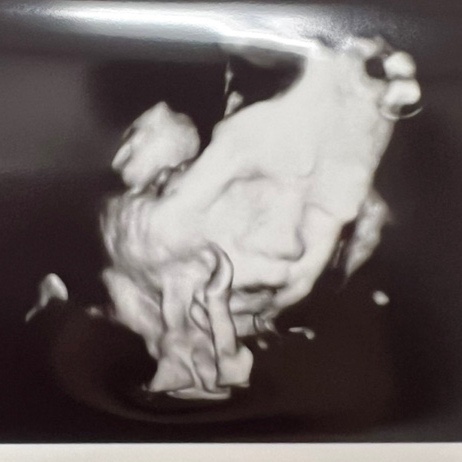

텔라동생 대작전 44 | 애플이가 쑥 큰 35주

2주 만에 애플이 무게재기! 다행히 2.2kg정도로 20프로까지 쭉 컷다! 33주엔 8프로여서 혹시나 태반 문제일...

텔라동생 대작전 42 | 8프로로 작은 애플짱 33주

나도 내 배가 신기해! 무더운 32주와 다르게 초가을 같았던 33주! 텔라랑 열심히 놀았다! 금욜에 4주만에 ...

맥북프로보다는 좀 작은 텔라동생 애플이 이번 검진에선 조금커서 30프로다! 저번엔 22프로여서 좀 걱정했...